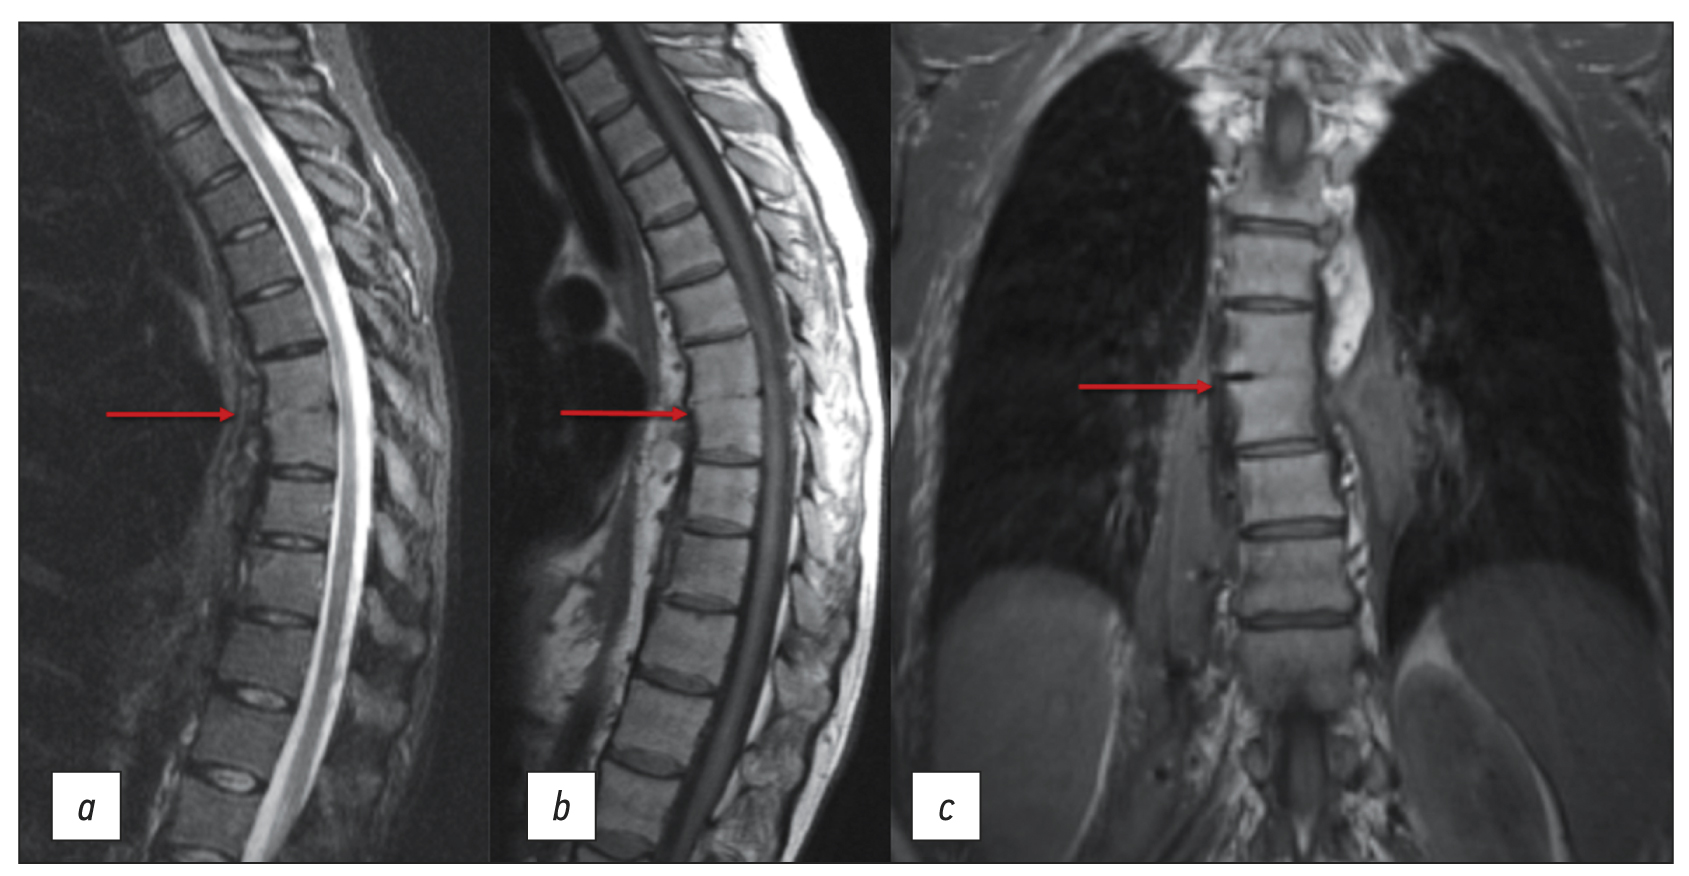

Chronic esophageal fistula as a rare cause of secondary osteomyelitis of the thoracic spine

Abstract

Infectious diseases affecting the spine are inflammatory destructive diseases that involved the organ and its structural elements as a result of infection by hematogenic, lymphogenic, or contact pathways, including may be a complication of surgical intervention. In arriving at an accurate diagnosis, it is extremely important to evaluate the anamnesis, the clinical picture, as well as the data of laboratory studies and radiation diagnostics in the aggregate.

This article presents a clinical case with the development of secondary ThVII–ThVIII vertebral spondylitis due to esophageal fistula. At the initial diagnosis, spondylitis was associated with spinal anesthesia performed six months prior to onset of the disease, as there was a fistulous defect on the skin in the lumbar region. Consequently, surgical interventions were performed three times in a surgical hospital at the place of residence. The data from the endoscopic examination, as well as the patient’s complaints regarding the relationship between meals, the appearance of pain, and the nature of the discharge from the fistula were not taken into account by doctors initially. With the help of an additional examination, including computed tomography of the esophagus with oral contrast and computed tomography fistulography, the main diagnosis was esophageal fistula. Thoracic spondylitis was only a secondary complication.

Thus, the final diagnosis of back pain and fistula in the lumbar region should be formulated after differential diagnosis with alternative diseases of the spine.

403-410